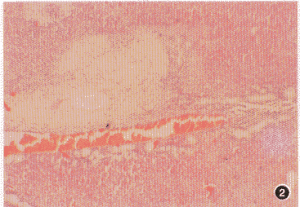

發病機制主要有以下幾種學說:①內膜損傷及平滑肌細胞增殖,細胞生長因子釋放,導致內膜增厚及細胞外基質和脂質積聚。

②動脈壁脂代謝紊亂,脂質浸潤並在動脈壁積聚:

③血流衝擊在動脈分叉部位造成的剪下力,或某些特殊的解剖部位(如股動脈的內收肌管裂口處),造成的慢性機械性損傷。主要病理表現為內膜出現粥樣硬化斑塊,中膜變性或鈣化,腔內有繼發血桂形成,最終使管腔狹窄,甚至完全閉塞。閉塞病變大致可分為:主-髂型、股-膕型、以及累及主-髂動脈及其遠側動脈的多節段型。患肢發生缺血性病變,嚴重時可引起肢端壞死。